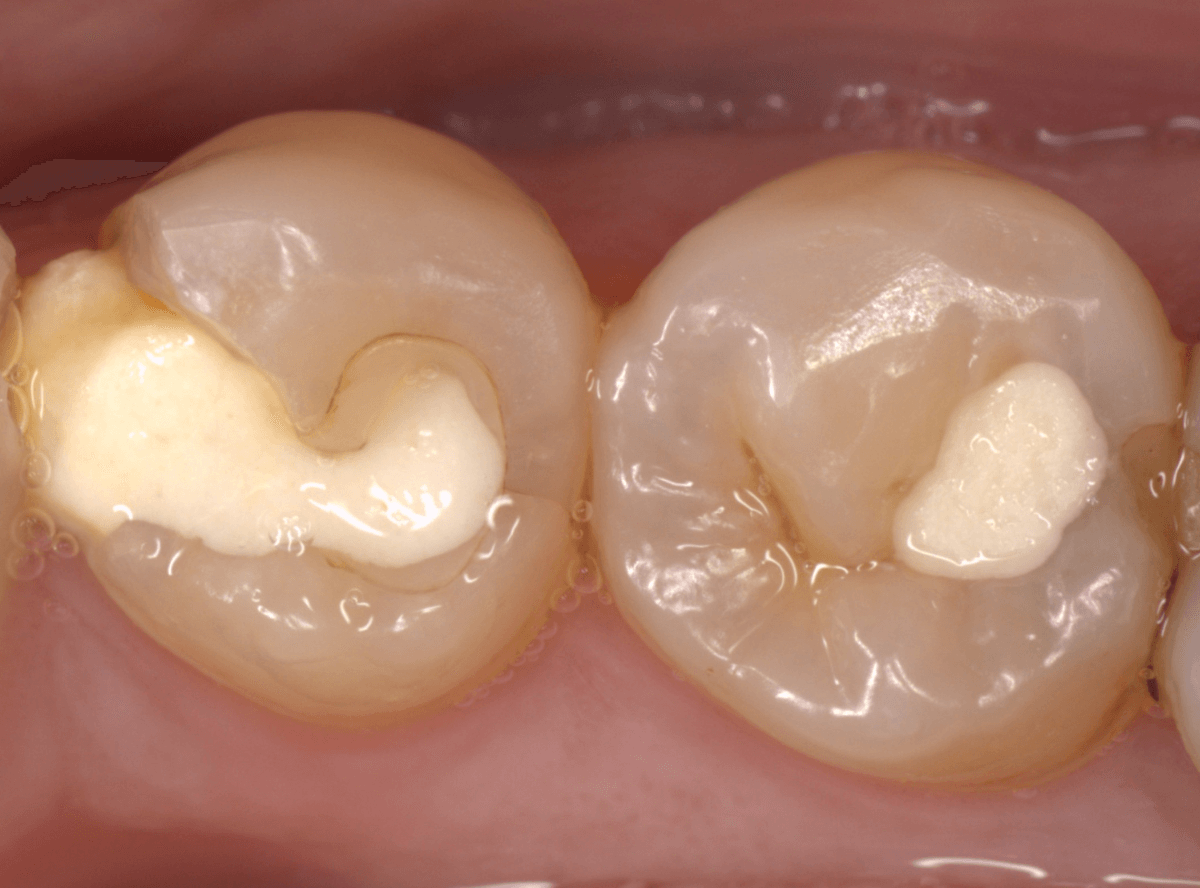

Case.26 4歯連続したセラミック・インレー

4本連続して歯と歯の間の虫歯を治療した患者さんのケースです。

虫歯を再発させないためには、歯と歯のすき間を物がつまらないよう、精密に再製する必要があります。

患者さんのご希望により、セラミック・インレーで修復する事になりました。

模型上で歯と歯のすき間を精密に再現・調整できるのが、セラミック・インレーの大きな利点です。

歯をトリミングして、型を取ります。

模型上で精密に製作します。

最終setした状態です。

左側の大臼歯2本が、ジルコニア・インレー

右側の小臼歯2本が、E-MAX・インレー

になります。

見た目にほとんど遜色ない仕上がりにできました。

普段あまりしない、4歯連続のインレー治療でしたが、精密に仕上げ・setする事が出来てホッとしました。